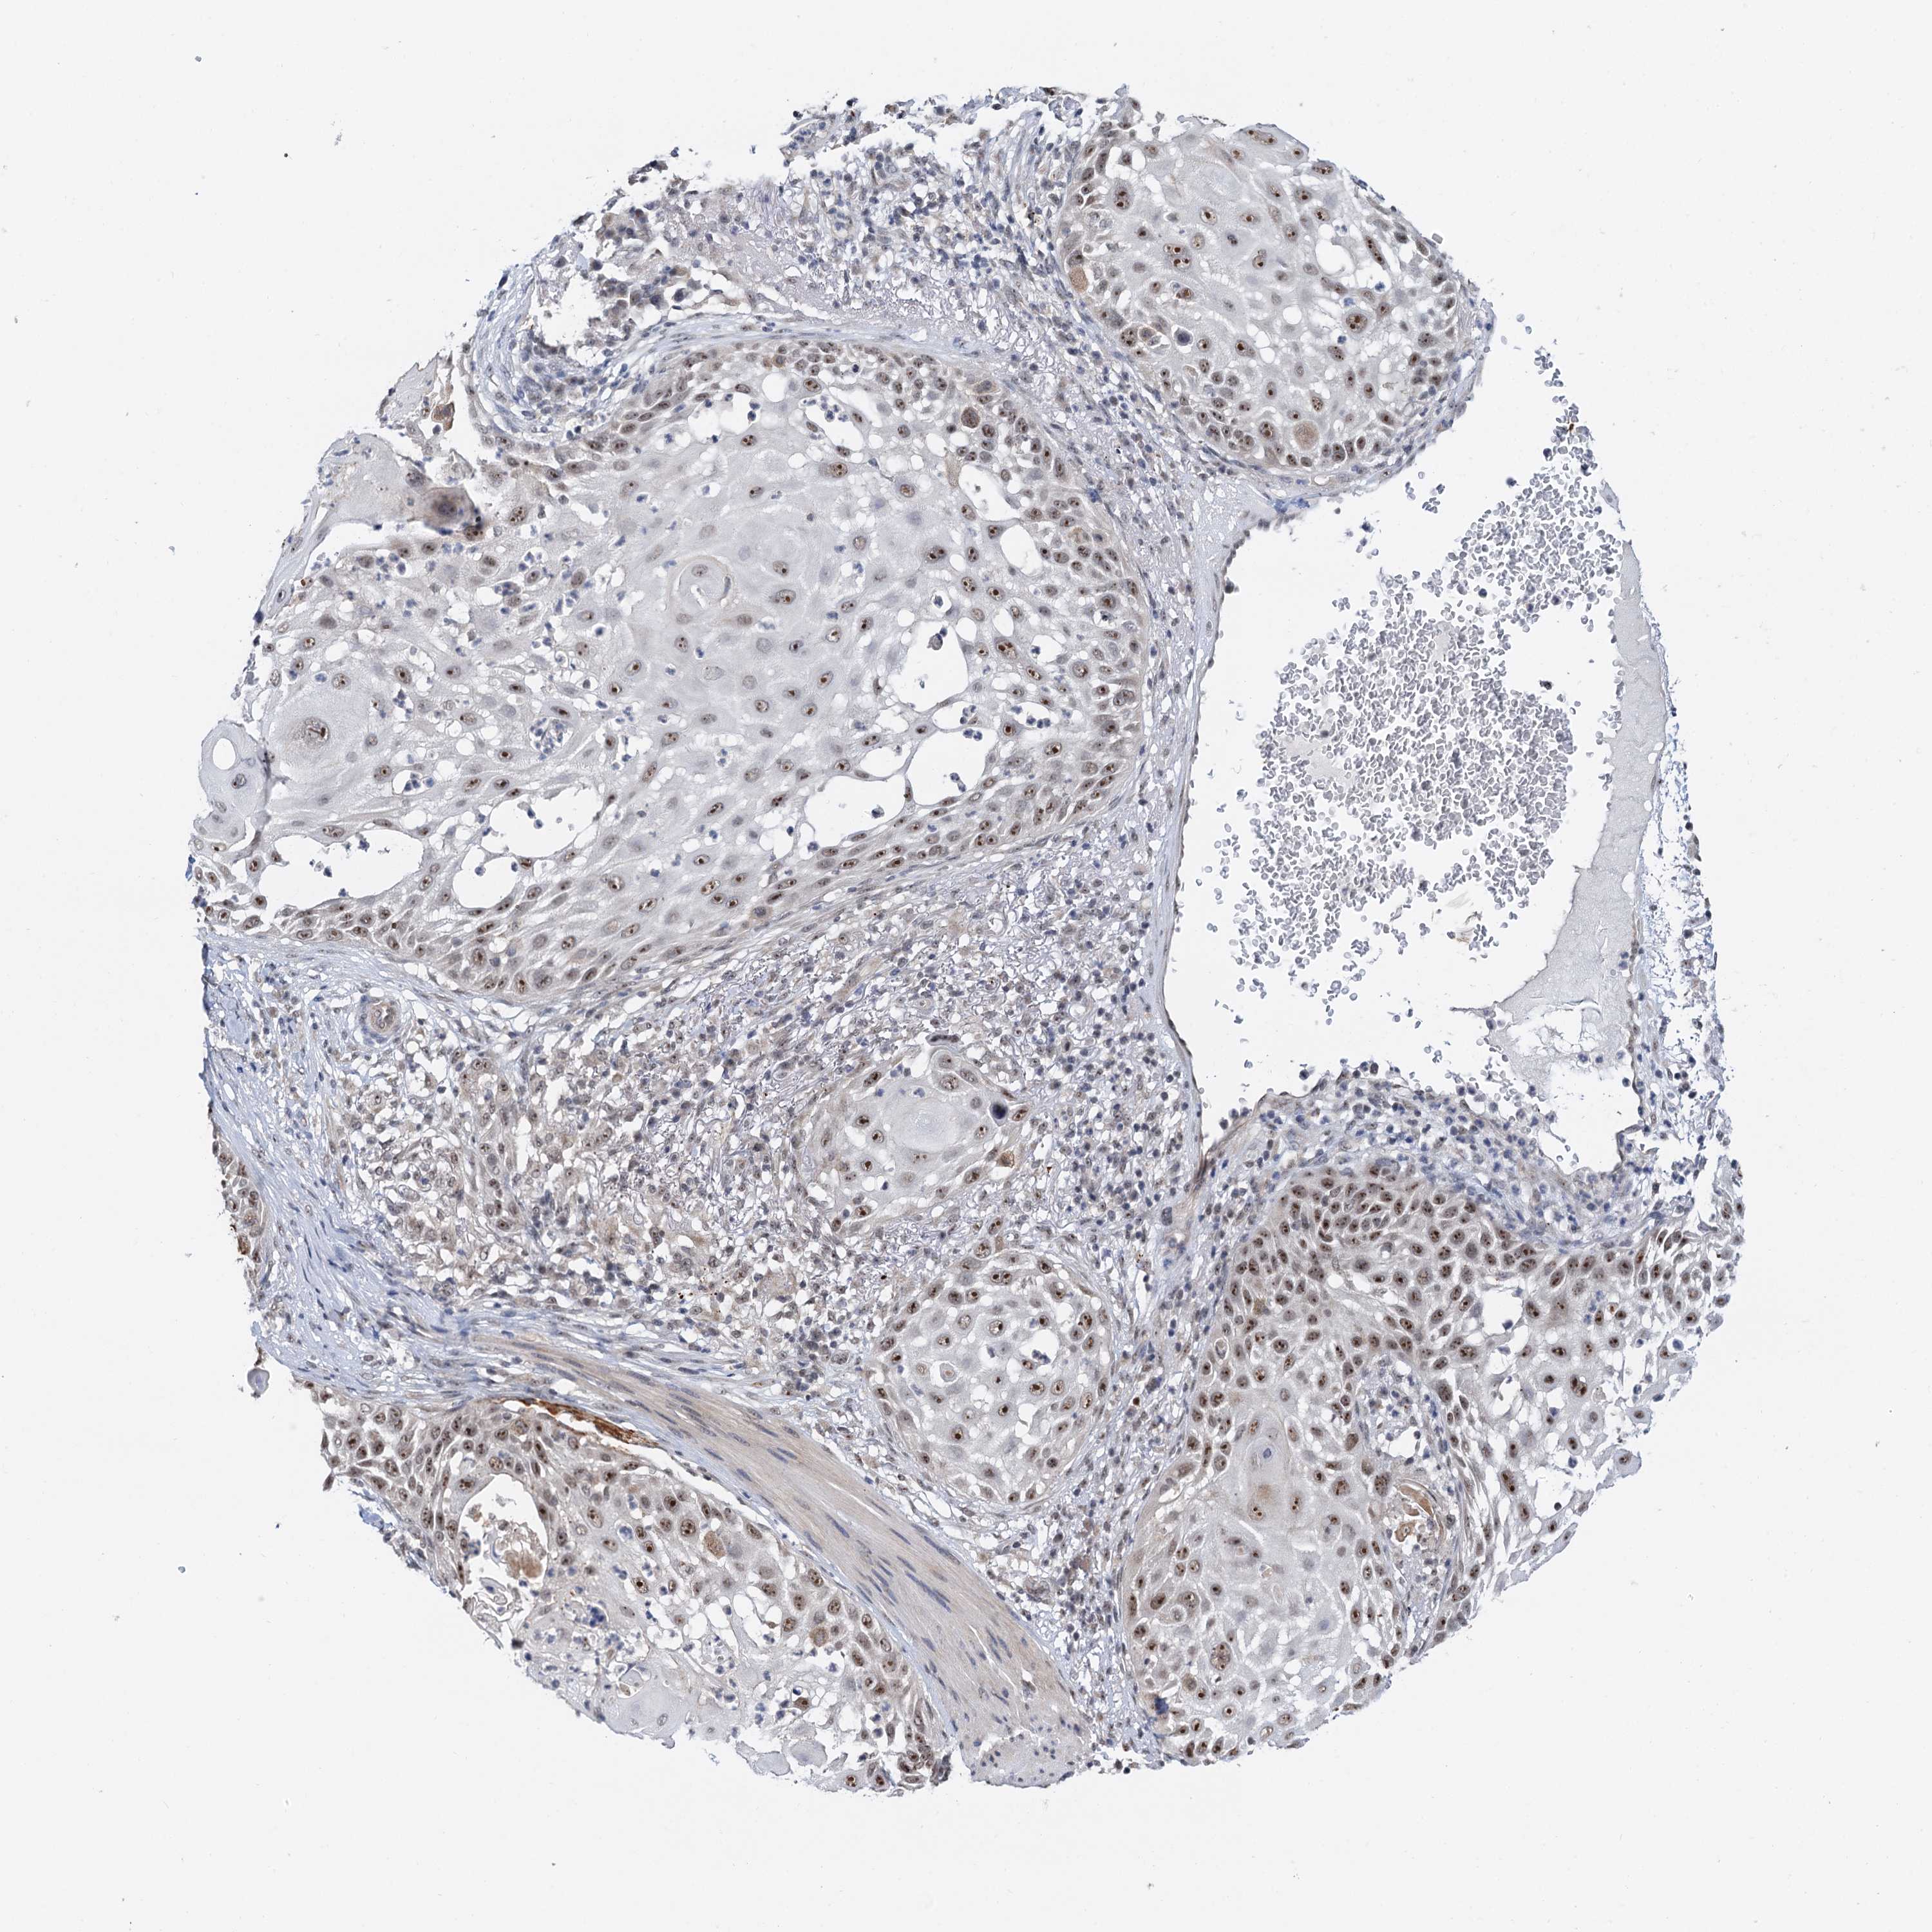

CANCER SKIN CANCER Show tissue menu

Basal cell and squamous cell cancer

SKIN CANCER - Protein expressioni

A mouse-over function shows sample information and annotation data. Click on an image to view it in a full screen mode. Samples can be filtered based on level of antibody staining by selecting one or several of the following categories: high, medium, low and not detected. The assay and annotation is described here.

Each image is clickable and will lead to virtual microscopy that enables deeper exploration of all samples and also displays staining intensity scores, fraction scores and subcellular localization as well as patient and tissue information for each sample.

Antibody CAB035546

Staining

High

Intensity

Strong

Quantity

>75%

Location

Nuclear

Basal cell carcinoma

Squamous cell carcinoma, NOS

Squamous cell carcinoma, metastatic, NOS